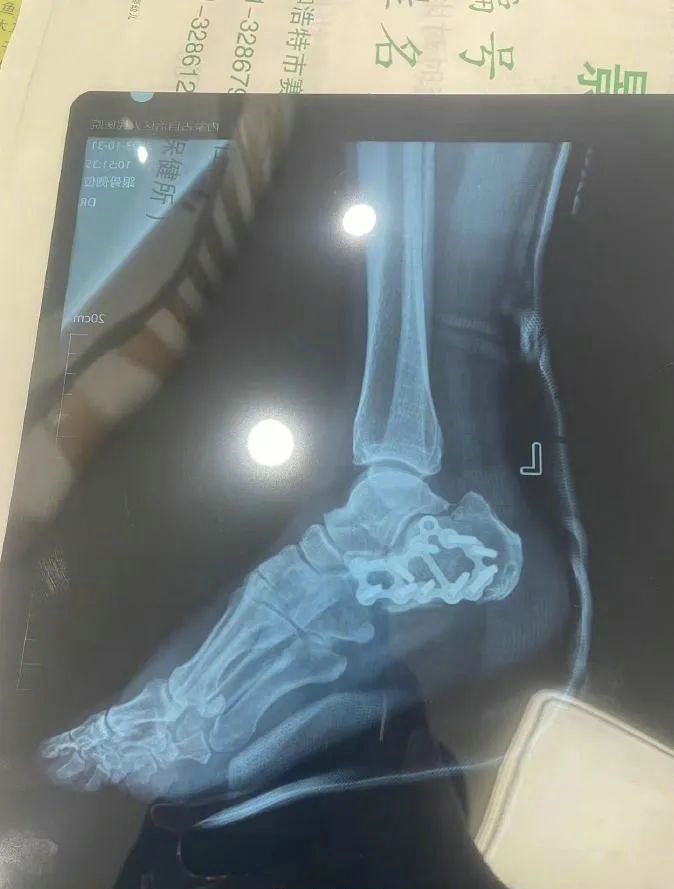

“那時(shí)候我剛工作了兩天,在第三天10月22日下午施工過(guò)程中從三層高的鐵架上摔了下來(lái),導(dǎo)致30厘米左右的鋼筋刺穿我的右側(cè)臀部,左腳跟也粉碎性骨折,被送往內(nèi)蒙古自治區(qū)人民醫(yī)院救治,當(dāng)晚做了手術(shù)取出刺在右臀部的鋼筋,10月30日又進(jìn)行了左腳粉碎性骨折手術(shù)?!崩紫壬嬖V記者。

據(jù)雷先生介紹,當(dāng)時(shí)內(nèi)蒙古騰龍建設(shè)工程有限公司許經(jīng)理問(wèn)過(guò)他賠付10萬(wàn)元能否解決問(wèn)題,他認(rèn)為這樣不太妥當(dāng)?!耙?yàn)槲业淖竽_骨折還要進(jìn)行二次手術(shù),并且我臀部受傷不能坐著,只能包車(chē)回家,會(huì)產(chǎn)生一系列的費(fèi)用?!崩紫壬f(shuō)?! ?/p>